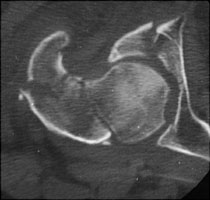

- Click on the image for a larger versionCAxial CT. This image from a different patient shows fractures of both columns of the acetabulum.